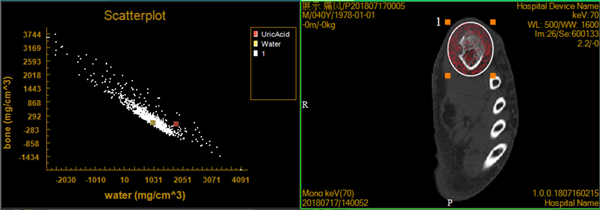

CT能谱成像是一种新兴技术,最早产生于20世纪70年代,但由于受到软硬件的限制而未能广泛应用。21世纪出现的以双kV为核心技术的能谱CT图像,为能谱成像的临床应用与研究创造了可能性。能谱CT是利用物质在不同X射线能量下产生的不同的吸收来提供比常规CT更多的影像信息的CT。与常规的单参数CT图像相比,能谱CT成像拥有涵盖多参数、定量分析的全新成像模式。

Precision 32精密断层能谱CT首次将目前高端CT具备的能谱成像技术广泛应用到32层CT,对常规CT难以定性的病灶和组织进行定性诊断和定量分析,提高诊断的精确度和安全性,将CT影像诊断成功率提升到一个全新的高度。